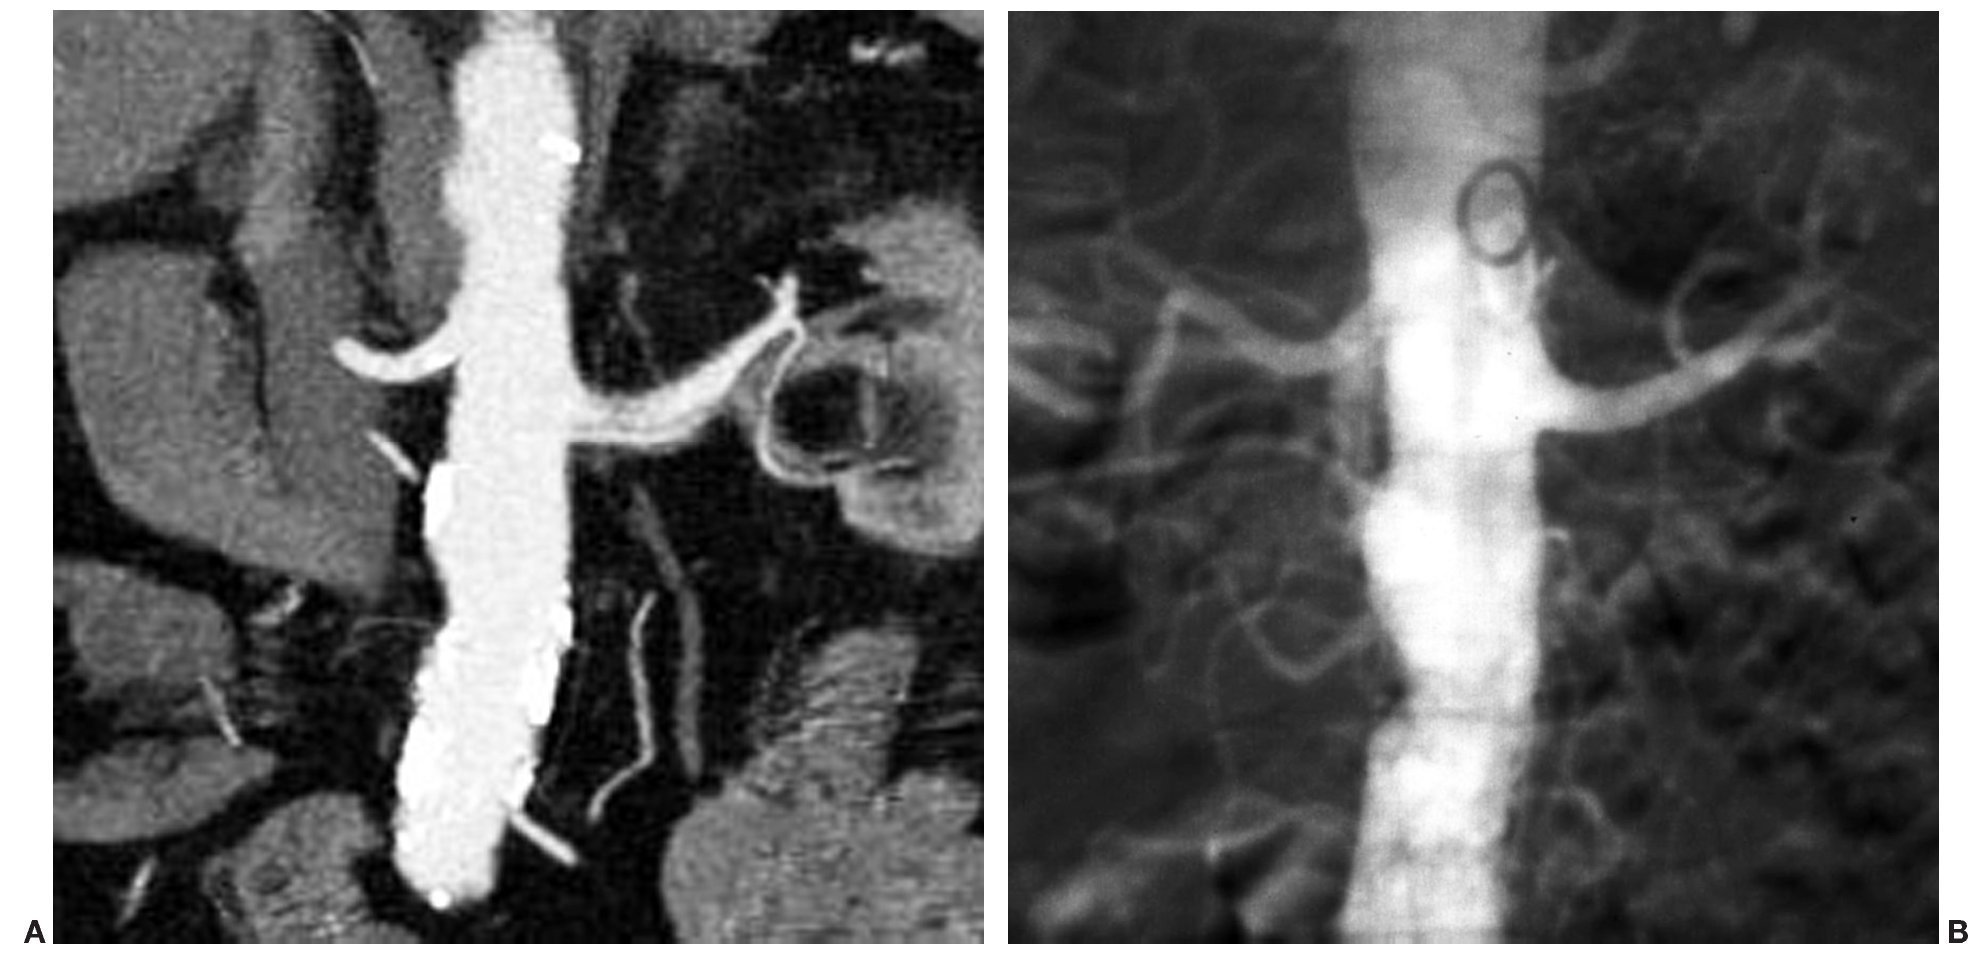

En TCMC se detectaron signos de displasia fibromuscular en tres arterias renales, y fueron clasificadas como estenosis de grado II. Estos hallazgos fueron corroborados tras la realización de la ASD. De los dos pacientes portadores de sendos injertos renales, en uno se diagnosticó correctamente una estenosis de grado III en la anastomosis quirúrgica de la arteria del injerto (fig. 3). En el otro paciente, la arteria del injerto presentaba un aspecto filiforme, en el límite de resolución de la TCMC. Se decidió, por tanto, cotejar su evaluación con la práctica de una ASD en la que se descartó de forma tajante una estenosis significativa potencialmente tratable. También se diagnosticó en la TCMC una disección espontánea de arteria renal, pero sin embargo esta lesión no se confirmó en la ASD (fig. 4). En el resto de casos en los que se detectó patología arterial se consideró la causa ateromatosa como factor etiológico.

Fig. 4. (A) Reconstrucción coronal de máxima intensidad de señal en la que se identifica una imagen de doble pared en la vertiente inferior de la arteria renal principal izquierda, que sugiere una disección espontánea. (B) En la angiografía con sustracción digital se observa una arteria íntegra y de características normales, descartándose el diagnóstico inicial de disección. El hallazgo muy probablemente fue motivado por un artefacto de vigoroso pulso arterial.

La relativamente baja especificidad de nuestra serie quizá se haya visto condicionada por el limitado número de pacientes derivado del criterio de inclusión en el estudio. De los 9 casos clasificados como FP, 4 ocurrieron en arterias con placas lipídicas con abundante presencia de calcio, lo cual corrobora la ya apuntada dificultad que entraña la valoración de las placas profusamente calcificadas. Otros 4 FP correspondieron a arterias con estenosis de grado I, pero próximas al 50%, lo que indica una cierta tendencia a la sobrevaloración que se hace especialmente patente en estas lesiones limítrofes. Finalmente, uno de los FP correspondió a una falsa disección. El origen de este diagnóstico erróneo pudo ser debido a un artefacto de movimiento motivado por el ciclo cardíaco y variaciones en el flujo arterial pulsátil, que, según se ha descrito, provocan movimientos en el tercio proximal de las arterias renales. Estos movimientos pueden mostrar una amplitud de desplazamiento craneocaudal de más de 2 mm, lo que es realmente significativo si se tiene en cuenta que las arterias renales principales miden unos 6 o 7 mm. Además, estos movimientos pulsátiles son más acusados en el lado izquierdo y en pacientes con HTA24. La importancia del conocimiento de este fenómeno radica en el hecho de evitar un falso diagnóstico de disección que pueda conducir a la adopción de actitudes terapéuticas urgentes innecesarias.